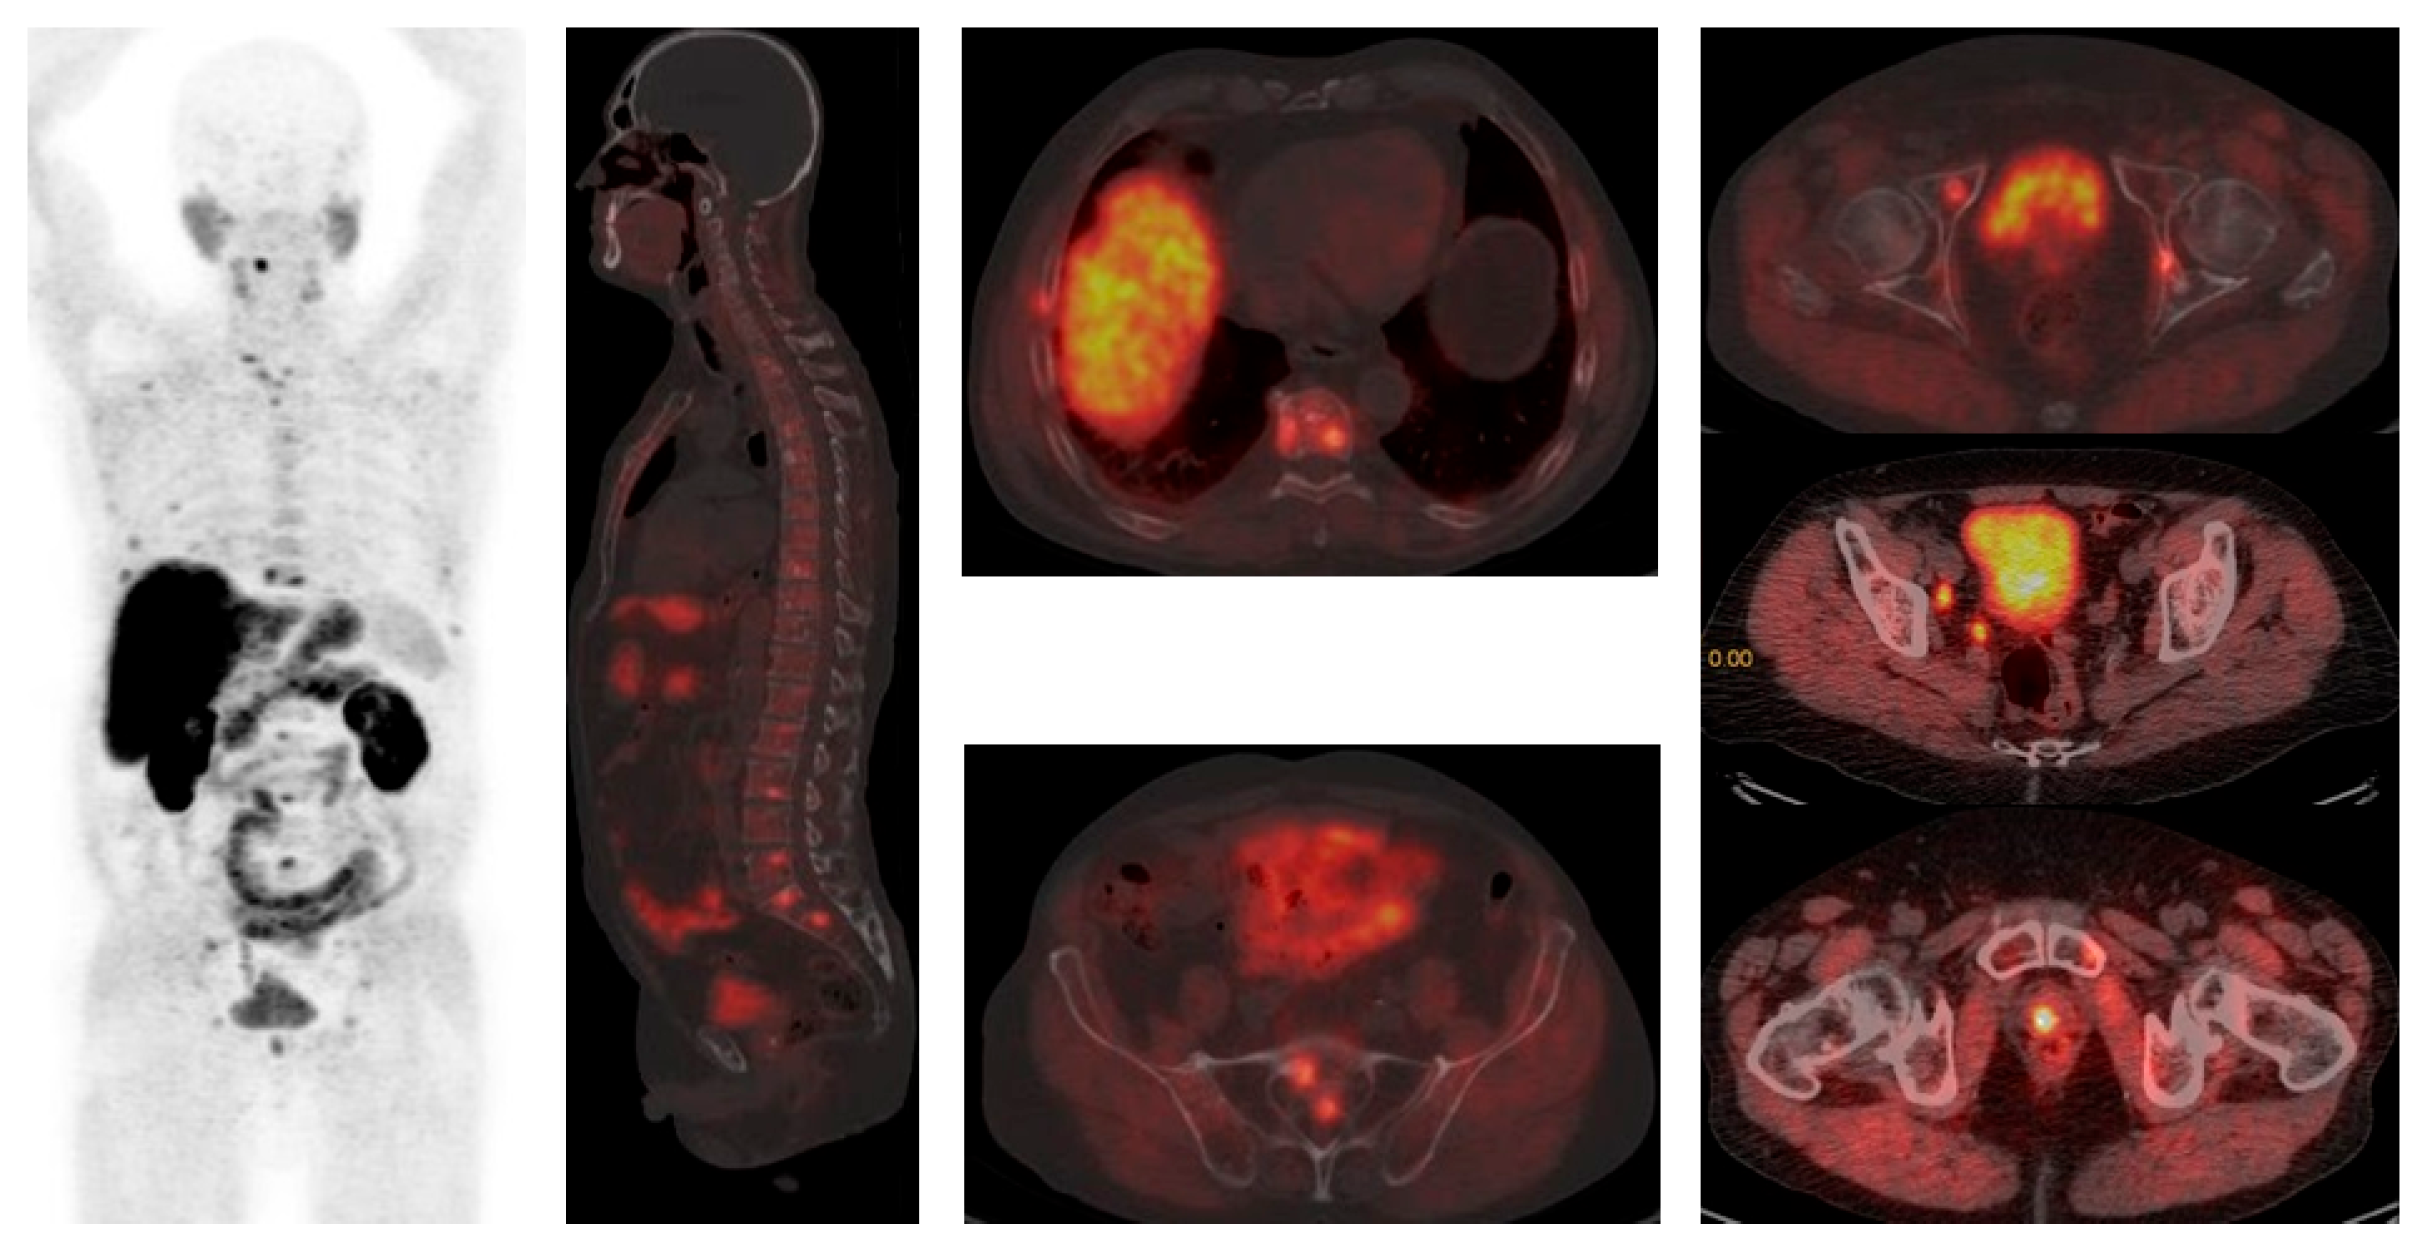

2.4. PSMA-Targeting Radiopharmaceutical PET/CT

4.3. Imaging in Metastatic Castration-Resistant Prostate Cancer (mCRPC)

4.4. Imaging in Therapy Response Evaluation